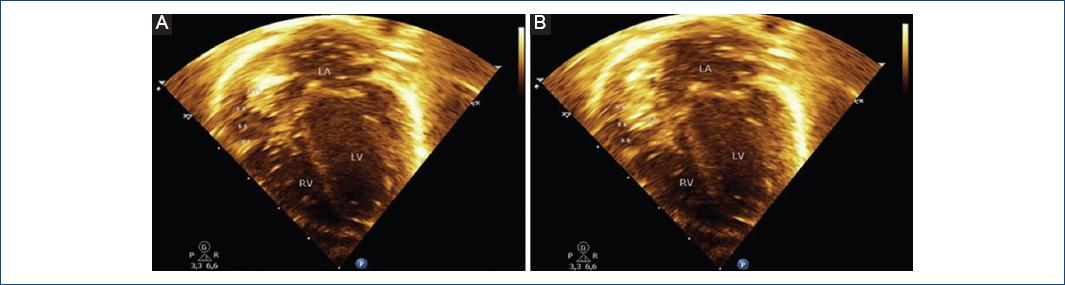

We present the case of a term newborn, with no significant perinatal history, who was taken to the emergency room at 18 days old for intermittent episodes of cyanosis, with no signs of respiratory distress, oxygen saturation of 85%, arterial gases with moderate hypoxemia, and normal chest X-ray. The transthoracic echocardiogram (TTE) revealed a large undulating membrane that divided the right atrium into two chambers and partially prolapsing through the tricuspid valve (Fig. 1A-D and Video 1). The caval veins drain into the posteromedial chamber, with part of its flow redirected by the membrane to the left atrium through the foramen ovale (Fig. 2A-D and Video 2). Contrast with an agitated saline solution was performed, observing initial accumulation of microbubbles in the posteromedial chamber (Fig. 3A-B).

Figure 3 A-B: Contrast echocardiography showing the initial accumulation of microbubbles in the posteromedial chamber.